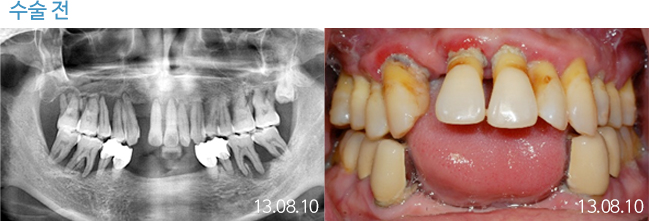

한 번 잘 심으면 10년 뒤에도 끄떡없는

더와이즈 임플란트

첨단 장비를 이용한 정확한 진단, 안정성이 입증된 정품 재료 사용,

노하우가 풍부한 숙련된 의료진의 시술 등이 임플란트 수명을 결정합니다.

※ 실제 본원에서 치료 받은 환자의 동의를 얻어 게재했습니다.

개인의 특성에 따라 부작용이 발생할 수 있으므로 담당의와 충분히 상의하시길 바랍니다.

THEWISE 치료별 전후사진